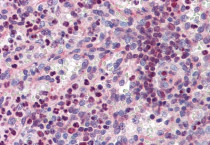

ARG64671 anti-PU.1 antibody IHC-P image

Immunohistochemistry: Paraffin-embedded Human spleen tissue. Antigen Retrieval: Steam tissue section in Citrate buffer (pH 6.0). The tissue section was stained with ARG64671 anti-PU.1 antibody at 3.75 µg/ml dilution followed by AP-staining.